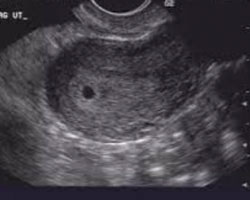

Em seguida oferecemos-te algumas imagens que não te vão deixar indiferente: uma ecografia da 4ª semana e um vídeo, para que possas ver o que acontece em movimento. Não percas!

Ecografia das 4 semanas

Se esta semana coincidir com uma consulta no ginecologista e este decidir fazer uma ecografia, esta já vai mostrar as paredes do útero (ou endométrio) mais grossas, apesar de ser quase impossível visualizar a vesícula gestacional.